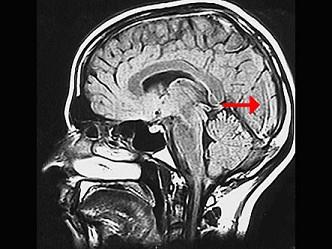

问题 如图箭头所示为大脑哪个部位 ( )

选项 A、颞叶 B、岛叶 C、枕叶 D、额叶 E、顶叶 一、单项选择题

答案 C